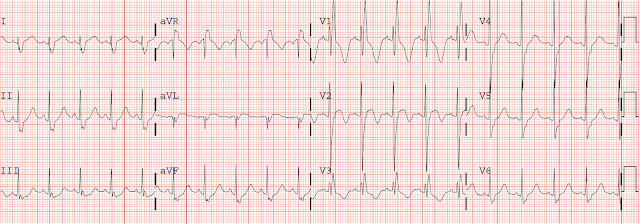

Because of this CT interpretation, they recorded an ECG:

It is clear that this transmural ischemia (STEMI/OMI) could have been diagnosed earlier with an ECG.

The ECG is all but diagnostic of LAD occlusion (Occlusion MI, or OMI)

Interesting case for this unfortunate young man who died from his severe head injury. The initial ECG in today's case (which I have reproduced in Figure-1) is markedly abnormal — with profound, coved ST elevation in not only the anterior leads — but also high lateral leads I and aVL + mirror-image opposite inferior lead ST depression (to the aVL ST elevation) + marked right axis (consistent with LPHB) + and not only loss of anterior R waves, but a fragmented downslope to the S wave in lead V3 (often itself a sign that there has been anterior infarction).

Dr. Smith lists 2 potential reasons to explain these ECG findings: i) Acute LAD occlusion; and, ii) Based on Echo findings — Takotsubo cardiomyopathy.

I would add a 3rd potential contributing factor = severe CNS injury — which is notorious for causing QTc prolongation with often unpredictable ST-T wave abnormalities that often result in “pseudo-infarct” patterns.

Obviously — severe CNS injury is not the only cause of ECG abnormalities in today’s case given marked Spectral CT and Echo abnormalities — but I thought the shape of elevated and depressed ST-T waves on today’s initial ECG to be distinctly unusual in the degree of T wave “fattening” (rounding out) at T wave peak and/or nadir (in those leads where the ST is depressed). I thought at least a portion of the unusual ECG findings in Figure-1 may be attributable to severe CNS injury.

| Figure-1: The initial ECG in today's case — obtained from a young man with severe blunt trauma with severe head injury (See text). |